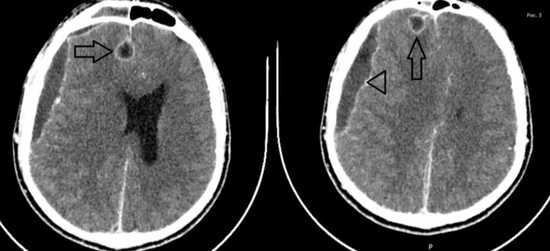

경막하농양(삼각)과 뇌농양(화살표시) MRI 영상경막하농양의 위치는 전두엽 부위에 많은데 대뇌표면을 따라 전파되거나 산발적인 농양을 형성할 수 있습니다.초기에는 수막염의 증상이 급속히 악화되어 의식 저하, 편마비, 발작 등이 있습니다.뇌농양의 경우는 크기가 커짐에 따라 뇌압 상승과 함께 대뇌 탈출, 농양 파열로 사망에 이릅니다.